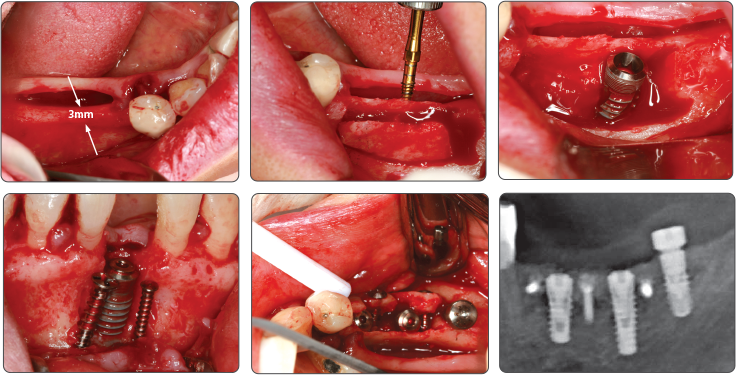

Recommend to use Sinus Lift Drill and Spreader Drill together

1. Sinus Lift (Ø4.0 Fixture)

Note

- Recommend to use Sinus Lift Drill and Spreader Drill together during the Sinus Lift operation.

- Easily operate by using Ø3.2 Spreader rather than Point Drill.

- Avoid to over press surrounding alveolar bone using Final Drill before fixture placement in D2.

ex) Ø4.0 Fixture placement